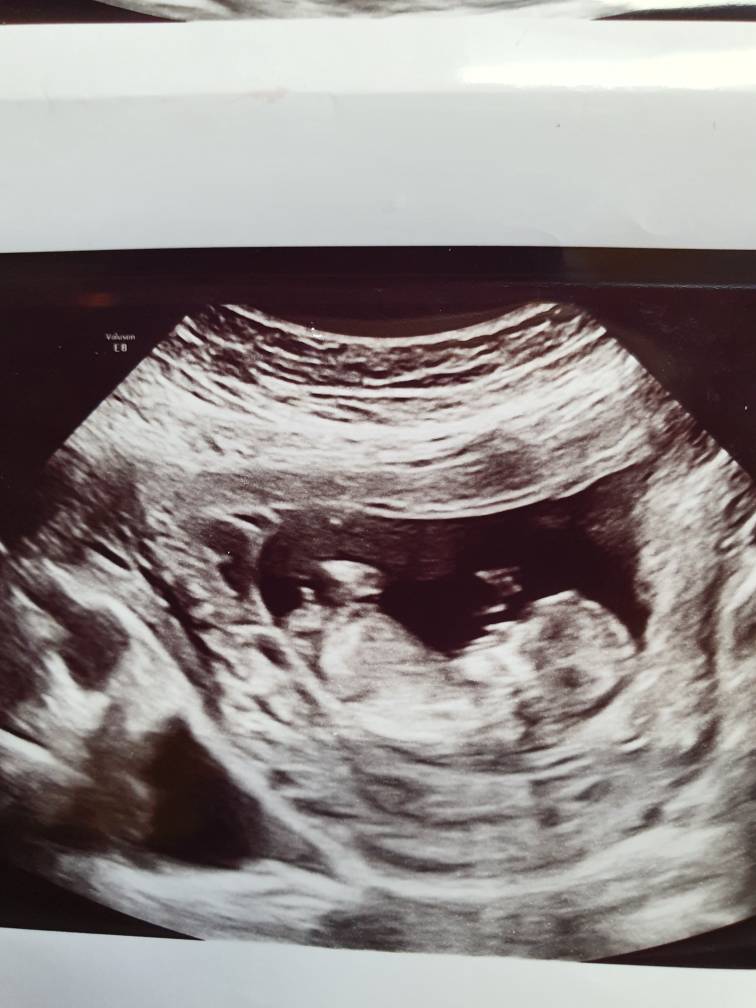

Can anybody give a guess on this.. Any nub is visible??I can't see anything. Verymuch excited to know what i am having

I'm afraid the nub isn't captured here - do you have any other shots?

Can you have a look at these pictures, any chance for a guess?? Thank you so much for your help[emoji3059]Attachment 43297Attachment 43300

The top pic looks boy but the bottom looks girl. I can't pin it down on the basis of these, sorry.